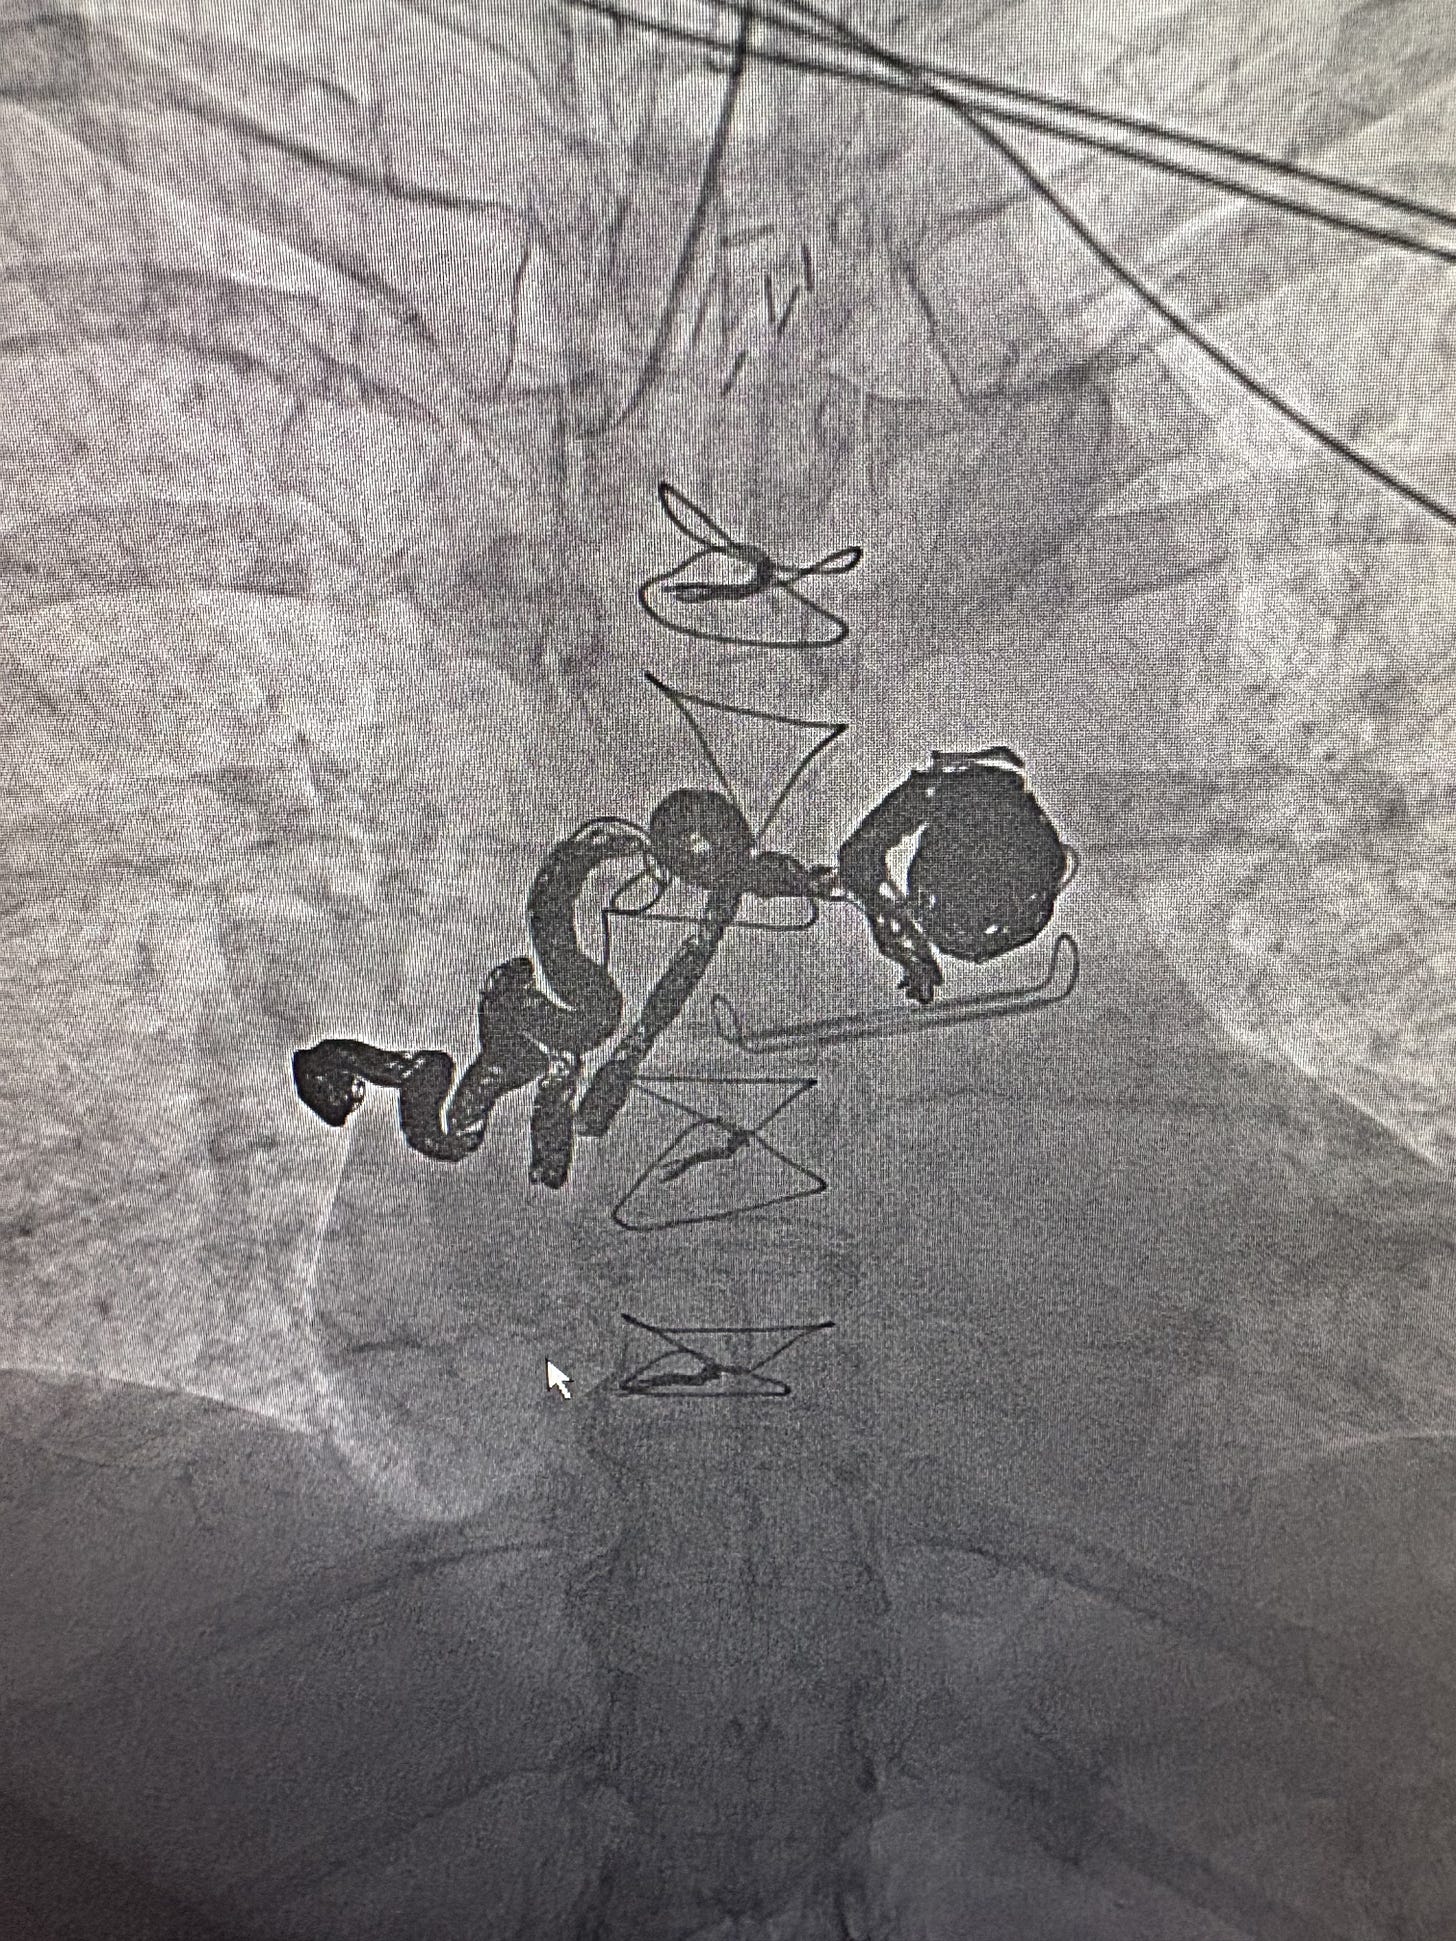

Now for the potentially boring part. Below are before and after images of my bronchial artery aneurysm and bronchial artery aneurysm to pulmonary artery fistula. As I probably mentioned on here before, each is rare, but to have them both together is “exceedingly rare.” Here’s the not boring, praise-the-Lord part: Prior to the procedure, the interventional radiologist planned to embolize the fistula as deeply as possible then see how I did and do the larger aneurysm later. But he was very happy he was able to fill nearly the whole squiggly, aneurysmal artery plus the bigger bulging artery. I now have 23 platinum coils in there. When I texted my oldest that information, he texted back, “Platinum is $2,000/oz now. Looks like me and Cam (sister) will be taking you to the pawn shop pretty soon.” So funny.